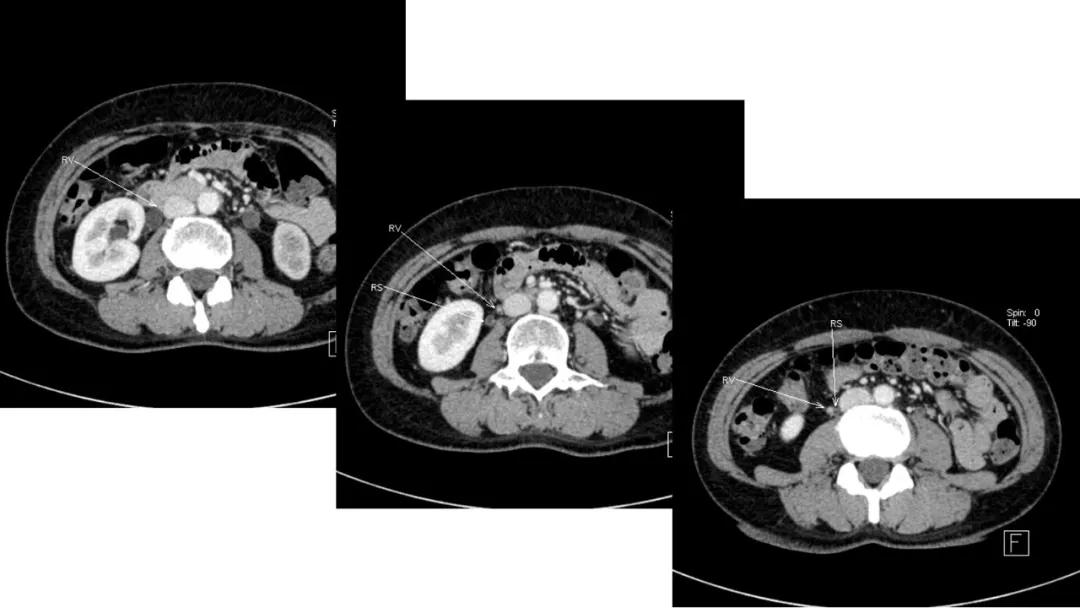

病理:浆液性囊腺癌

病理:颗粒细胞瘤